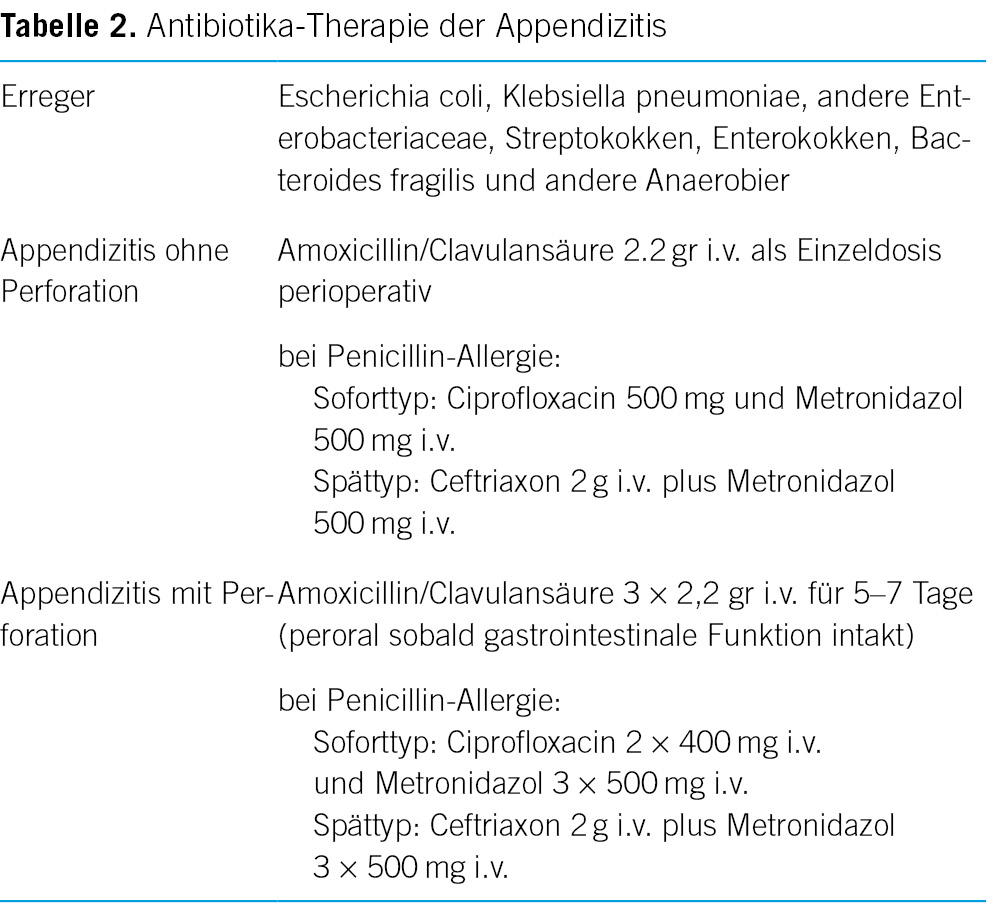

Antibiotika sind wichtige Bestandteile der Appendizitis, Therapie und sollten gegen Gram-negative Bakterien und Anaerobier wirksam sein (Tabelle 2). Die notwendige Dauer der Antibiotikatherapie im Rahmen der nicht-operativen Therapie orientiert sich hauptsächlich am klinischen Verlauf und der Dynamik der Entzündungsparameter; in der Regel wird vorerst eine parenterale Antibiotikatherapie über 1–3 Tage empfohlen, die für weitere 5–7 Tage mit oralen Antibiotika fortgeführt wird [2]. Perioperativ sollten Antibiotika immer, unabhängig davon, ob eine unkomplizierte oder komplizierte Appendizitis vorliegt, angewendet werden. Dadurch werden Wundinfektionen und Abszesse reduziert. Die postoperative Fortsetzung der Antibiotikatherapie über 5–7 Tage ist nur bei der komplizierten Appendizitis, vor allem beim Vorliegen eines Abszesses indiziert.